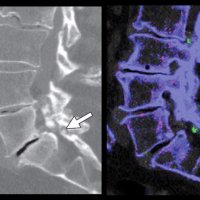

The fluid sign is one of the radiological features of osteoporotic fractures, and can be helpful in distinguishing them from metastatic vertebral fractures, as it is seen more often in osteoporotic fractures and is rarely seen in metastatic fractures.

In fractured vertebral bodies, the fluid sign was adjacent to the fractured end plates and exhibited signal intensity isointense to that of cerebrospinal fluid on a background of diffuse hyperintensity in the vertebral body because of acute collapse.

It is seen in acute vertebral compression fractures that show bone marrow edema. In osteoporotic fractures, the fluid sign was significantly associated with fracture severity.